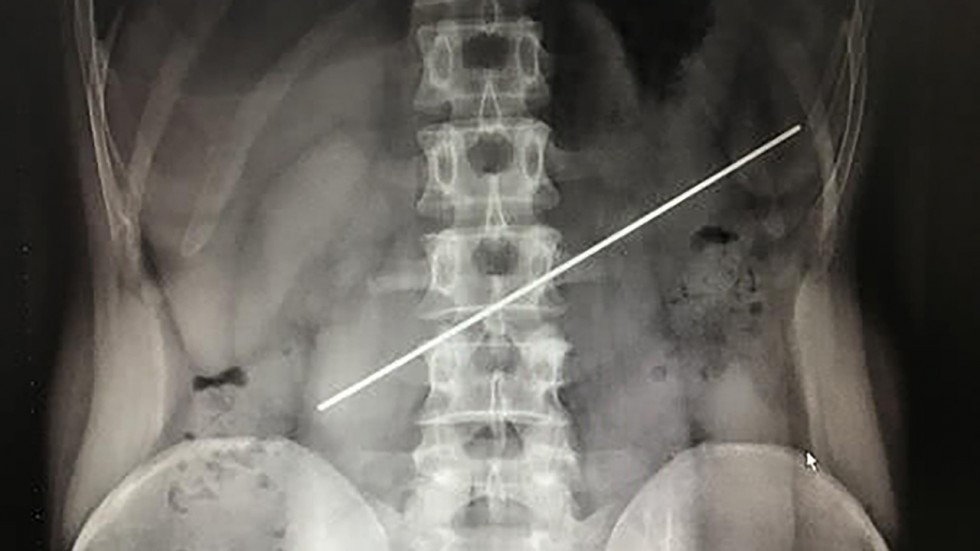

Médicos lograron extirparle una vara de acero del estómago a un hombre que la tragó como parte de una apuesta.

De acuerdo con medios locales, el paciente había "ingerido" el objeto de 20 centímetros hace un año.

Entonces, decidió a consultar con un especialista, quien le realizó una radiografía y observó que la varilla seguía alojada en su estómago.

Además, el médico detectó que uno de los extremos del objeto había perforado la pared gástrica.